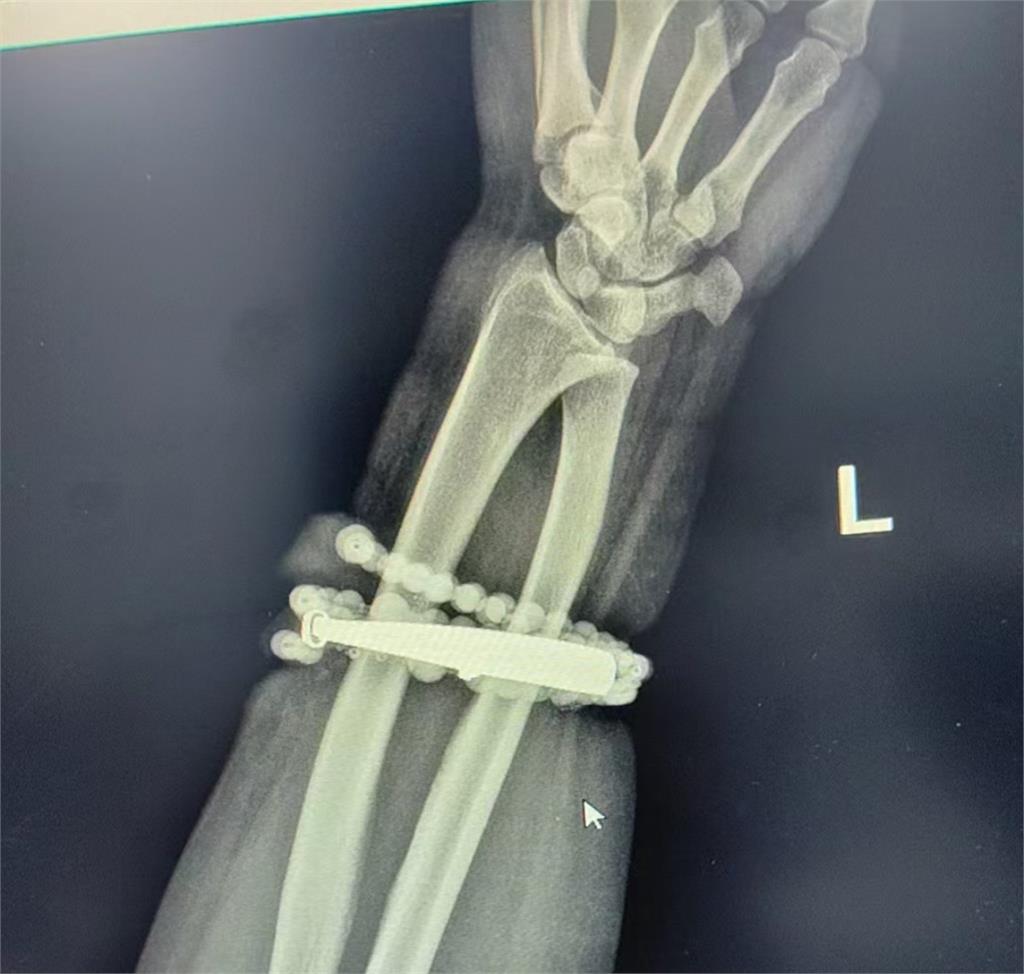

鞏女見事態嚴重,才終於決定就醫,寧德市閩東醫院創傷骨科及手顯微外科醫師表示,這是典型的首飾長期壓迫、摩擦,加上細菌感染,引發的慢性發炎和肉芽組織增生,手鐲已經成了一個不斷刺激皮膚、污染傷口的病灶,若不及時手術取出,感染恐會擴散至深層組織,甚至導致敗血症或手臂功能喪失,醫療團隊最後決定以手術的方式處理,經過多次討論與抗感染治療後,醫師為龔女實施「前臂異物取出及清創手術」,醫師形容整個過程如「考古挖掘」,在經過一個多小時手術後,醫生成功將手鐲和串珠從厚厚的增生組織中完整剝離出來,目前龔女恢復良好,已順利出院,她感謝醫師的救命之恩「真的太謝謝醫生了,我以為我的手保不住了!」。